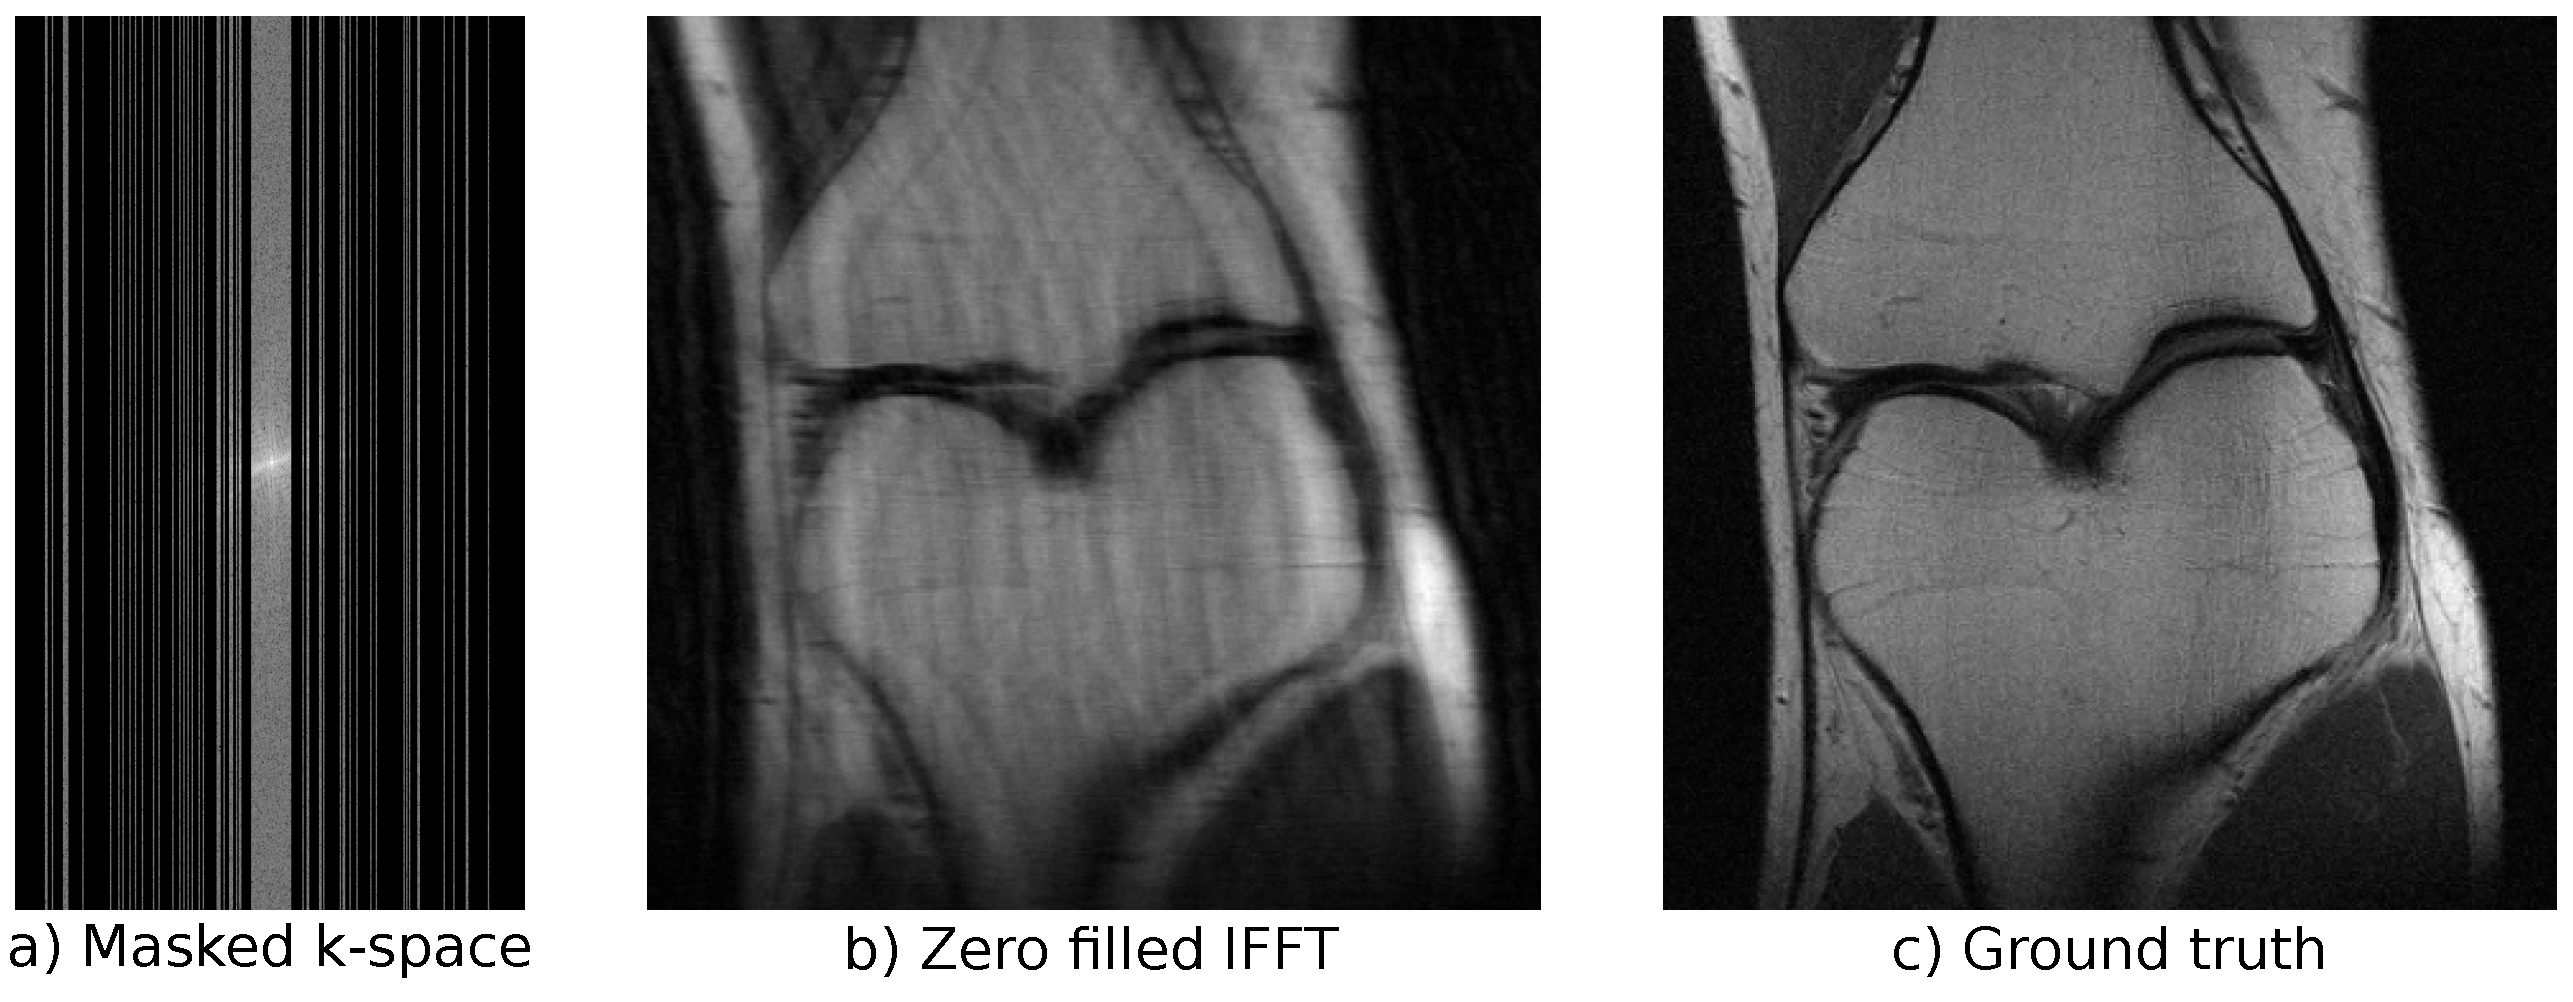

3.3. Magnetic Resonance Imaging

4.3. Magnetic Resonance Imaging